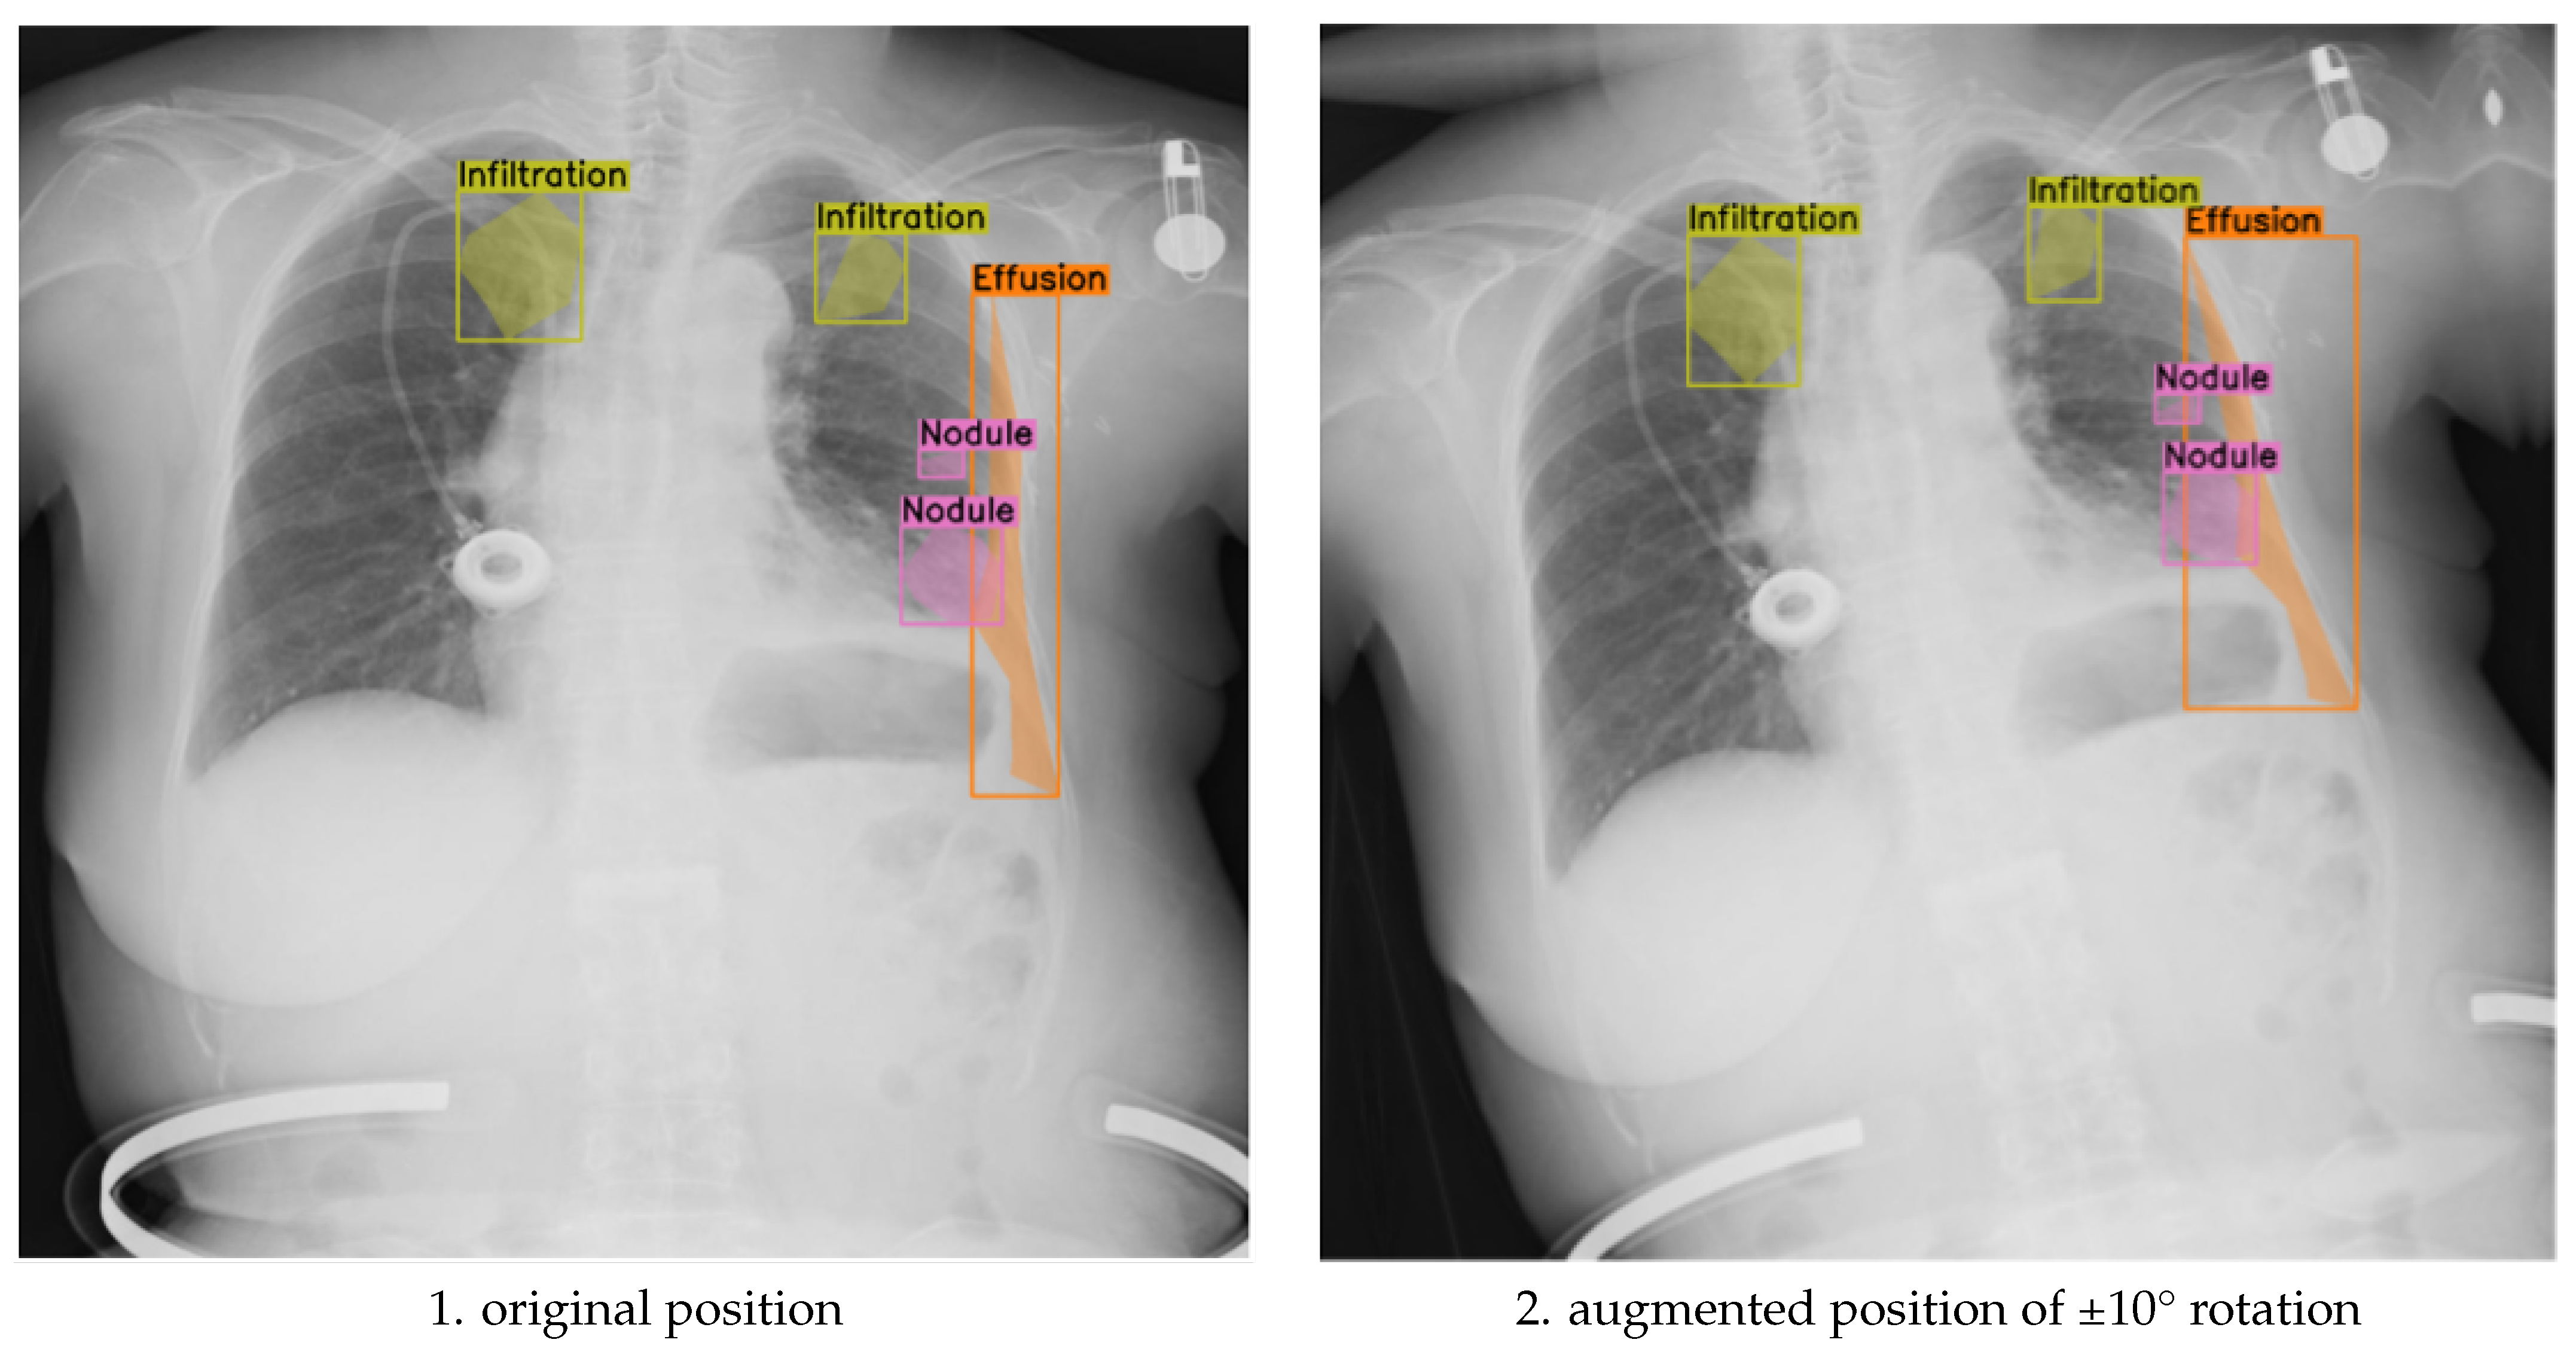

The purpose of this ablation design was to evaluate whether small-angle geometric rotation, when applied in conjunction with clinically constrained augmentation, contributes to measurable gains in segmentation precision and generalization. Previous studies often apply compound augmentations without considering their impact on anatomical alignment or label consistency. In contrast, our approach isolates the effect of rotation magnitude within a robust, expert-validated augmentation framework. This ensures that any observed performance differences can be attributed primarily to rotation, rather than to uncontrolled variation in other augmentation parameters. As illustrated in Figure 3, applying ±10° rotations introduces noticeable shifts in the spatial distribution of segmented pathologies, such as infiltration, effusion, and nodules, demonstrating that larger angular deviations can alter anatomical context and impact the alignment between pathological features and image landmarks.

To assess the balance between anatomical label fidelity and augmentation effectiveness, we further analyzed the model’s performance under the ±5° rotation component, within a broader augmentation strategy that also included translation, scaling, brightness adjustment, and Gaussian noise. This mild geometric transformation preserved anatomical relationships while introducing sufficient spatial variability, leading to measurable improvements in segmentation quality. As shown in Figure 4, the augmented images maintain clear boundary alignment and anatomical realism, particularly in regions affected by multi-label pathologies. Compared to both the unaugmented baseline and the more extreme ±10° augmentation, the ±5° approach yielded smoother contours, improved lesion localization, and enhanced generalization across diverse patient presentations.

Figure 3. Comparison of original and discrete rotations at (−10°, +10°) augmented chest X-ray images.

Figure 4. Comparison of original and discrete rotations at (−5°, +5°) augmented chest X-ray images.